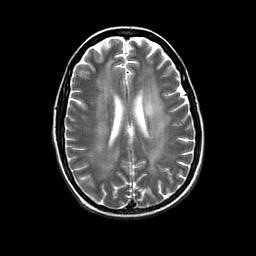

МРТ головного мозга. Аксиальная Т2-взвешенная МРТ. Расширение борозд и диффузные очаги.

Прогрессирование атрофии при прослеживании МРТ головного мозга в динамике происходит очень быстро.

МРТ головного мозга. Т2-взвешенные аксиальные МРТ типа FLAIR. Динамика очагов за полгода.